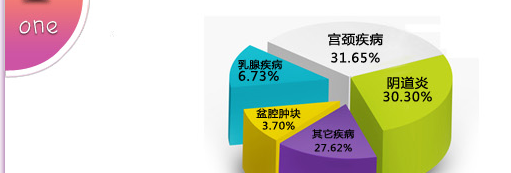

| 据国内外的医学料统计表明:已婚女性的健康问题中,76.8%由各种妇科疾病及乳腺疾病引起;近10年来,女性不孕、宫颈癌和乳腺癌发病率发病率平均每年增长2.3%。 |